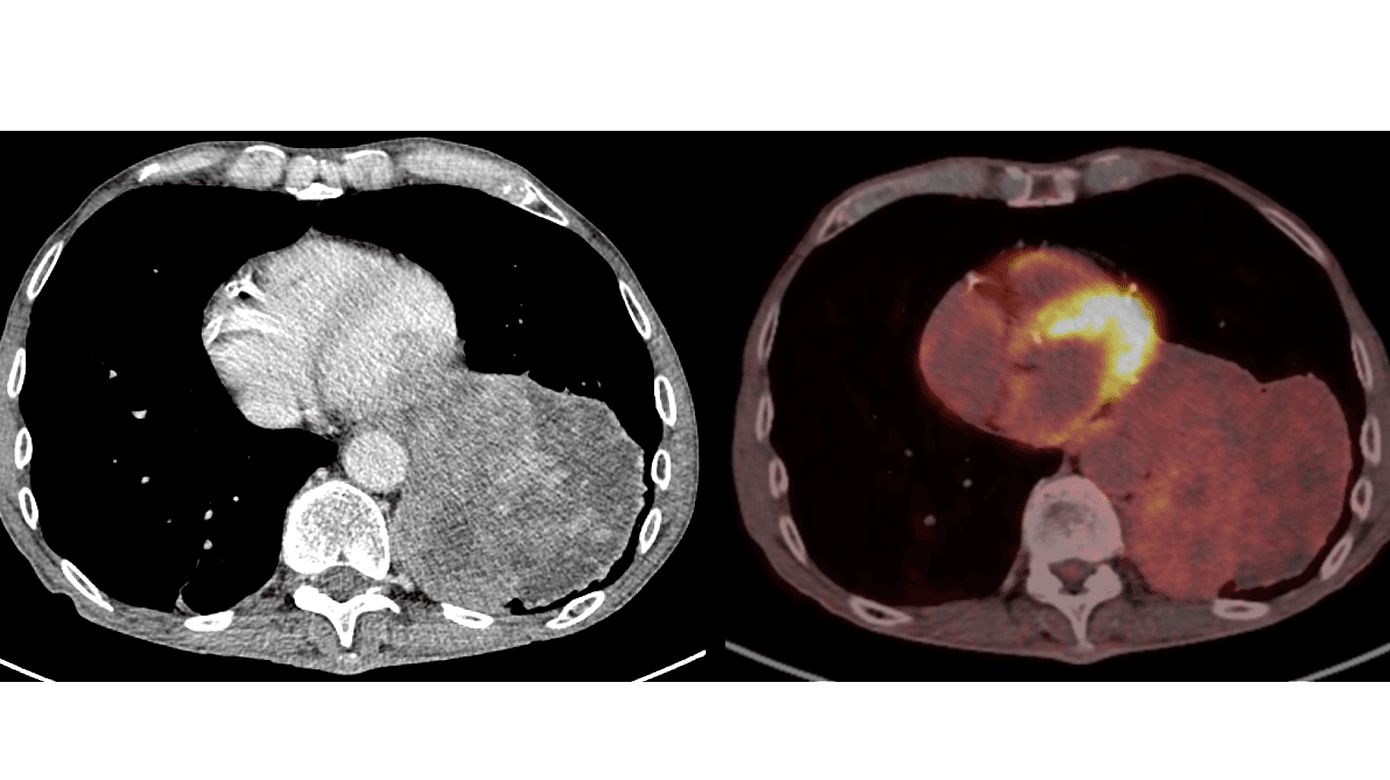

CT viste en heterogen tumorproces, der inddrog næsten hele venstre underlap uden tegn til invasion af de omgivende strukturer (Figur 1A). PET med lavdosis-CT viste kun svag fluordeoxyglukose (FDG)-optagelse forenelig med lavmalign proces (Figur 1B). De efterfølgende nålebiopsier fra tumoren blev vurderet bedst forenelige med SFT.

På grund af tumorernes variable udseende og forskellige lokalisationer i thorax kan CT-fund ved SFTP være diagnostisk udfordrende. Større SFTP er typisk heterogene, som hos patienten i sygehistorien, og i disse tilfælde kan både benigne og maligne SFTP minde om andre maligne processer [4]. PET-CT kan muligvis bidrage til at differentiere mellem SFTP og andre maligne lidelser, og mindre studier har vist svagere FDG-optagelse ved maligne SFTP sammenlignet med andre maligne tumorer i thorax [4]. En endelig diagnose kræver dog histologisk bekræftelse [1].